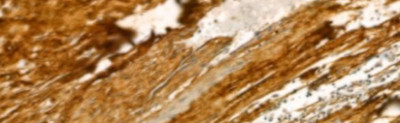

IHC (Immunohiostchemistry)

(AAA323015 at 1/100 staining Human Melanoma tissue by IHC-P. The sample was formaldehyde fixed and a heat mediated antigen retrieval step in citrate buffer was performed. The sample was then blocked and incubated with the antibody for 1.5 hours at 22 degree C. An HRP conjugated goat anti-rabbit antibody was used as the secondary.)